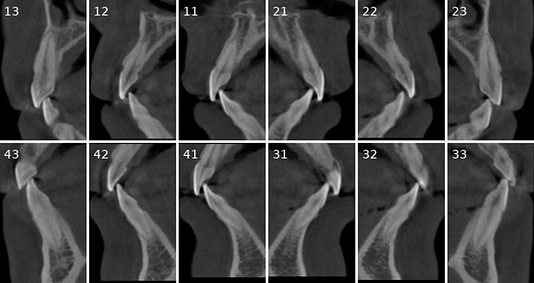

Tooth number is selected to analyze the root canal morphology within the CBCT radiograph.

Sagittal and coronal slices and highlighting the angle/curvature/length of the canals.

Measurement of periapical radiolucency volume is a unique advantage with 3D CBCT versus 2D PA. These are endodontic reports for tooth 12 which had a very large periapical radiolucency. The reports were done before and after a long-term calcium hydroxide dressing.